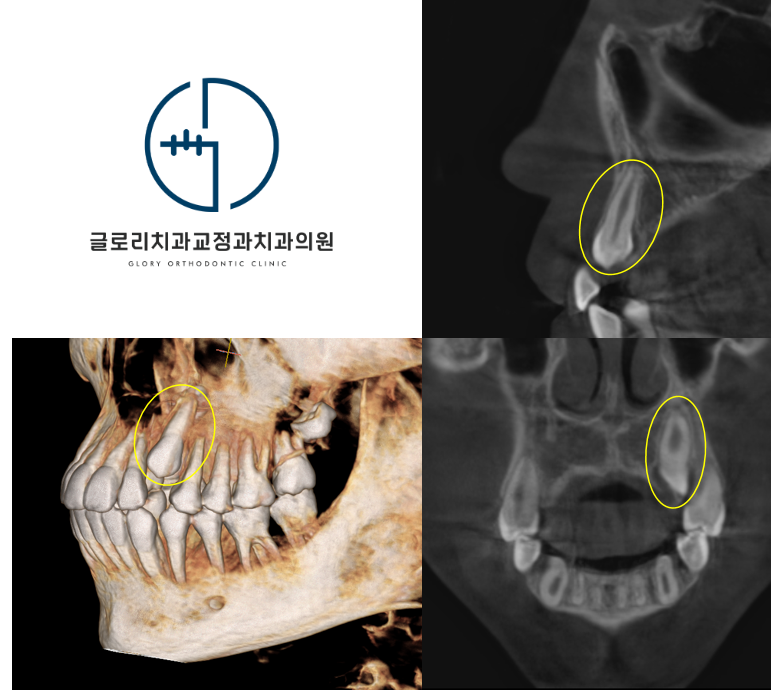

그러나 매복된 송곳니의 정확한 위치와 주변 치아 뿌리와의 관계를 확인하려면 CT 촬영이 필수적으로 병행되어야 합니다.

3차원 영상 자료를 통해 매복치가 입천장 쪽에 위치하는지 아니면 입술 쪽에 매복되어 있는지를 명확하게 구분할 수 있습니다.

이 위치에 따라 치료 방향이 달라지기 때문에 초기 진단의 정확성이 중요합니다.